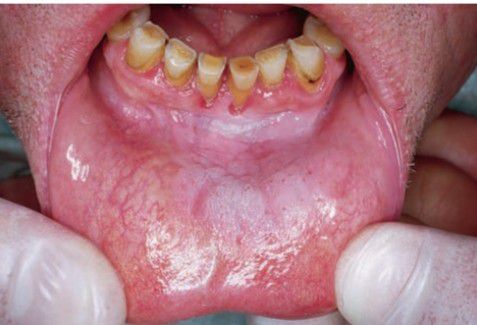

Snuff dipper's pouch

Asymptomatic white folds surrounding area where tobacco is held; usually found in labial and buccal vestibules.